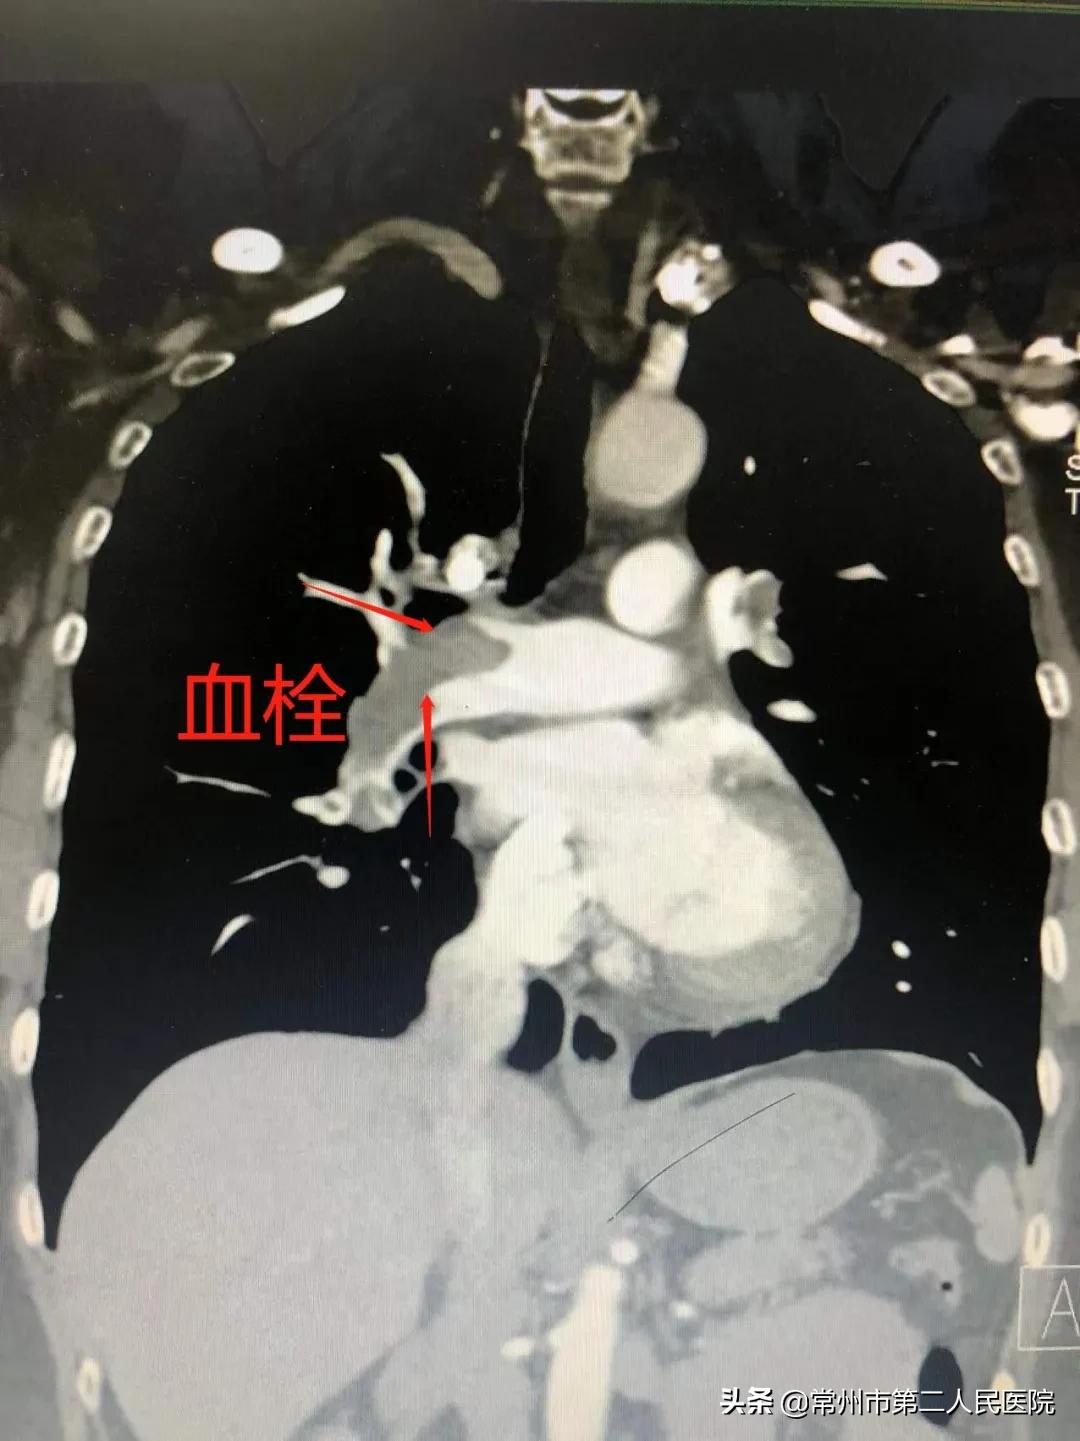

二院城中院区急诊120病房主任顾体军团队接诊后,为周先生立即行持续胸外按压、心肺复苏,并予气管插管。在紧张而有序的抢救后,周先生终于恢复了心跳呼吸,但生命体征仍不平稳,有明显胸闷、气喘症状。根据多年的急救经验判断,顾体军认为患者可能是肺栓塞了,紧急联系放射科进行肺动脉CT血管造影检查,结果显示患者双侧肺动脉栓塞,同时下肢血管彩超提示左下肢深静脉血栓。

肺动脉CTA